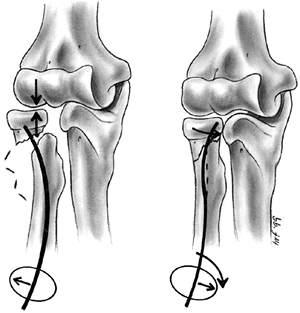

nerve function. Neurovascular problems are frequent, and fracture

management may be altered if neurovascular compromise is present. In

the absence of neurovascular compromise, displaced fractures can be

splinted and managed safely in a delayed manner as long as the child is

closely monitored (132,133). Primary CRPP is the preferred treatment for type III injuries (134) (Fig. 33.18).

Displaced supracondylar fractures treated by closed reduction and

casting have a higher incidence of residual deformity than those

treated with reduction and pinning (134). Closed reduction and casting also has a higher risk of Volkmann ischemic contracture than treatment with early pinning (134).

experience has demonstrated that two or three laterally placed pins are sufficient for stabilization (137).

The authors prefer laterally placed pins without a medial pin except in

unusual circumstances. When a medial pin is used, one should be aware

that extreme elbow flexion could result in ulnar nerve subluxation from

its groove and increase the risk of damage during pinning. When

possible, it is advisable to place the lateral pin first to provide

provisional stability so that the medial pin can be inserted with the

elbow in less than full flexion, placing the ulnar nerve farther

posterior. It is also advisable to make a small incision over the

medial epicondyle and dissect with a hemostat, so that the medial pin

can be placed directly on the bone. Anatomic alignment is preferred,

but this may be difficult to achieve in some cases. When the quality of

reduction is in doubt, comparison radiographs of the opposite elbow can

be obtained intraoperatively. The Baumann angle should be within 5 to 8

degrees of the angle on the contralateral side. As long as fixation is

secure, it is the author’s opinion that one may accept up to one-third

translation of the distal fragment, 30 degrees of malrotation, and 20

degrees of extension after pinning (capitellum anterior to the anterior

humeral line). Initial immobilization should be in a nonconstrictive

splint or cast with the elbow in less than 90 degrees of flexion. The

authors prefer a cast that has been bivalved and spread with the elbow

in approximately 70 degrees of flexion. Oral analgesics are usually

sufficient for pain relief. The need for intravenous narcotics may

indicate ischemia. Immobilization is continued for 3 to 4 weeks, at

which time the pins are removed and active range of motion is initiated.

![]() |

|

Figure 33.18 Type III supracondylar humerus fracture. A: This type III fracture demonstrates lateral displacement. B:

The lateral projection also shows flexion of the distal fragment. The treatment of this less common position is the same as that for extension fractures. The posterior periosteum is torn, and hyperflexion of the elbow will excessively forward-flex the distal fragment. The elbow is best pinned at slightly less than 90 degrees of flexion, because it is technically difficult to pin the elbow in extension. C and D: Anteroposterior and lateral postreduction and pinning films. |

reduction through a medial approach, adding a lateral incision, if

necessary. An anterior surgical interval can also be used, and is

recommended if the neurovascular structures need to be exposed. The

posterior approach should

be

used cautiously because it disrupts any remaining intact soft tissue

and may disrupt the primary vascular supply to the distal humeral

fragment (122,123).

Complete vascular disruption is uncommon, because the thick local

muscle envelope protects the artery. Vascular evaluation after

reduction requires differentiation of the pulseless extremity that is

pink and viable from one that is cold and pale with vascular

insufficiency. The child who has a well-perfused hand but an absent

radial pulse after satisfactory closed reduction does not necessarily

require routine exploration of the brachial artery (129,138,140,141).

The pulse usually returns within 48 hours. Likewise, the absence of a